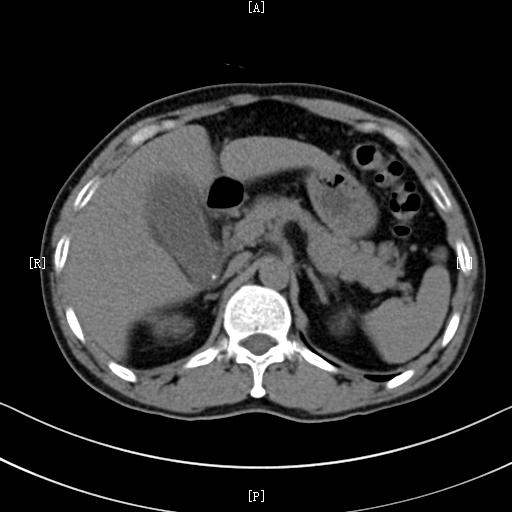

如果出现上述类似的症状,建议及时到医院筛查排出肝脓肿。主要的检查项目常常为 查血和超声检查 。实验室查血检查常常 白细胞计数明显增高 ;超声检查常常可以 明确其部位和大小 ,阳性诊断率可以达到95%以上,是首选检查;当然, 必要时也可以做CT检查 ,CT检查能够全面评估病灶以及周围脏器的情况,是非常好的一项辅助检查方法。

肝脏肿瘤的疼痛常常不是特别典型,所以及时筛查非常重要,对于肝癌,主要的筛查方法包括: 查血清甲胎蛋白(AFP),超声检查,CT检查和MRI检查 。AFP对肝癌有比较高的特异性,很多肝癌患者都有AFP的升高;而影像学的超声,CT和MRI检查是诊断肝癌以及其他肝脏肿瘤最主要的方法。

急性胆囊炎常常通过医生的 体格检查,结合查血,超声及CT检查 可以确诊。体格检查常常会有右上腹胆囊区域的压痛;查血常常会有白细胞的升高,而超声和CT检查可以观察胆囊大小,胆囊壁是否增厚,胆囊周围有无水肿,是诊断胆囊炎必不可少的辅助检查。

3、胆囊及胆道肿瘤。比如胆囊癌、胆管癌之类的。肿瘤引起的腹痛常常没有特异性,以隐痛比较多见。如果继发了胆囊炎,还可能和胆囊炎症状类似。所以对于胆囊肿瘤,最好的方法还是通过影像学检查明确。比较好的检查方法是CT或者MRI检查。

对于肠道穿孔,体格检查一般会有明显的腹膜刺激征,而比较好的辅助检查是 腹部立位平片 ,如果发现有膈下游离气体,一般可以确诊;而如果是比较少的游离气体,可以通过 腹部CT检查 确诊。

而如果怀疑是肾脏疾病,可以考虑进行 超声以及CT检查 ,影像学检查仍然是发现肾脏疾病最主要的方法。